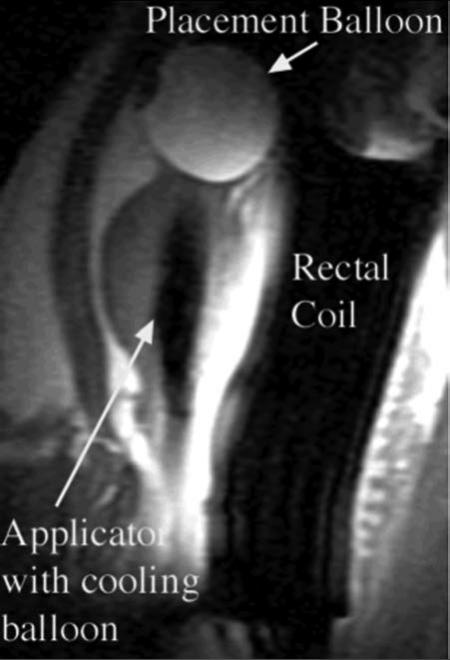

MRI-compatible interstitial ultrasound applicators which may be inserted directly into the prostatic parenchyma have also been evaluated, as described by Nau et al.40-44 in vivo. A schematic diagram of such an applicator is provided in Figure 2B. A typical device consists of an array of 2 or 3 cylindrical piezoelectric elements having outer diameter (OD) of 1.5 mm. and lengths of 10 mm. The outer surface of the transducers were sectored to produce an insonation pattern of roughly 180 degrees, and were operated in a similar frequency range to the transurethral devices, of 7 to 8 MHz. The technical details of these studies are described in much more detail elsewhere39,40,44,45 As noted above, among the critical roles of MR imaging in thermal ablation of the prostate using ultrasonic applicators is the ability to guide precise positioning of the transurethral and interstitial applicators within the prostate prior to the ablative procedure. Rapid MR imaging sequences, including spoiled gradient recalled (SPGR) and rapid T2 weighted sequences such as single-shot fast spin echo (SSFSE) can be used repeatedly to monitor device positioning to assure good placement. Transurethral devices, for example, are positioned within the gland, and secured in place by filling the small retention balloon at the entrance to the urinary bladder (Figure 3). As will be shown below, directional interstitial devices may be inserted in any portion of the prostate gland to achieve directed ablation of any desired tissue region.

Figure 3.

Sagittal SPGR T1-weighted image from study of ablation of a canine prostate using a transurethral applicator incorporating a cooling balloon within the prostate. The device uses circulating water to cool both transducers and the prostatic urethra. A placement balloon in the urinary bladder, containing dilute gadolinium contrast to enhance visualization, retains the applicator in position. The rectal coil arrangement both enhances SNR for prostatic imaging, and incorporates circulating water for rectal cooling.